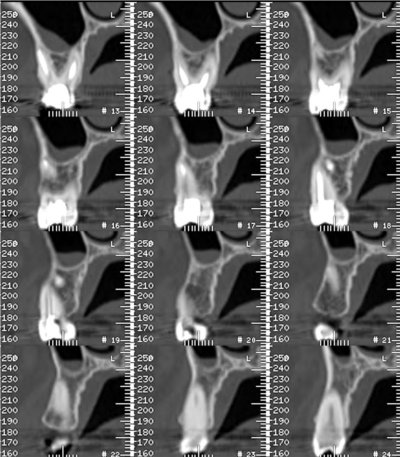

Les nouvelles générations de scanner permettent de faire une acquisition d’un volume global d’une partie du corps et de travailler à l’intérieur de ce volume en isolant une structure anatomique donnée et de l’explorer dans tous les plans de l’espace.

Grace à la technique de seuillage il est possible de dissocier progressivement les dents des structures osseuses environnantes dans le volume donné.

- Vues : 24801